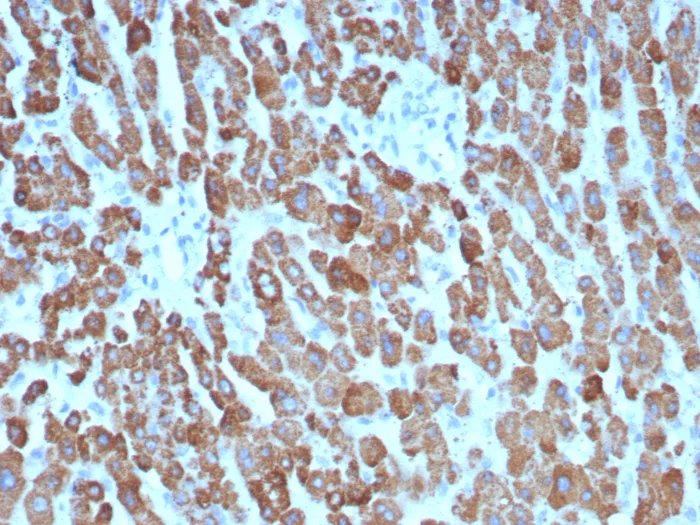

Formalin-fixed, paraffin-embedded human hepatocellular carcinoma stained with CPS1 Mouse Monoclonal Antibody (CPS1/8416). HIER: Tris/EDTA, pH9.0, 45min. 2°C: HRP-polymer, 30min. DAB, 5min.

This MAb recognizes a protein of 165kDa, identified as carbamoyl phosphate synthetase 1 (CPS1). This mitochondrial enzyme catalyzes synthesis of carbamoyl phosphate from ammonia and bicarbonate. This reaction is the first committed step of the urea cycle, which is important in the removal of excess urea from cells. �Deficiency of CPS1 is an autosomal recessive disorder that causes hyperammonemia. CPS1 is a hepatocyte specific protein that localizes to the mitochondria of hepatocytes. It is a sensitive marker for distinguishing hepatocellular carcinomas (HCC) from other metastatic carcinomas as well as cholangio-carcinomas. HCC s occur primarily in the stomach, but they are also found in many other organs. CPS1 may also be a useful marker for intestinal metaplasia. Reportedly, strong expression of CPS1 correlates with smaller tumor size and longer patient survival. Occasionally, CPS1 is also found in gastric carcinomas as well as in a few other non-hepatic tumors.